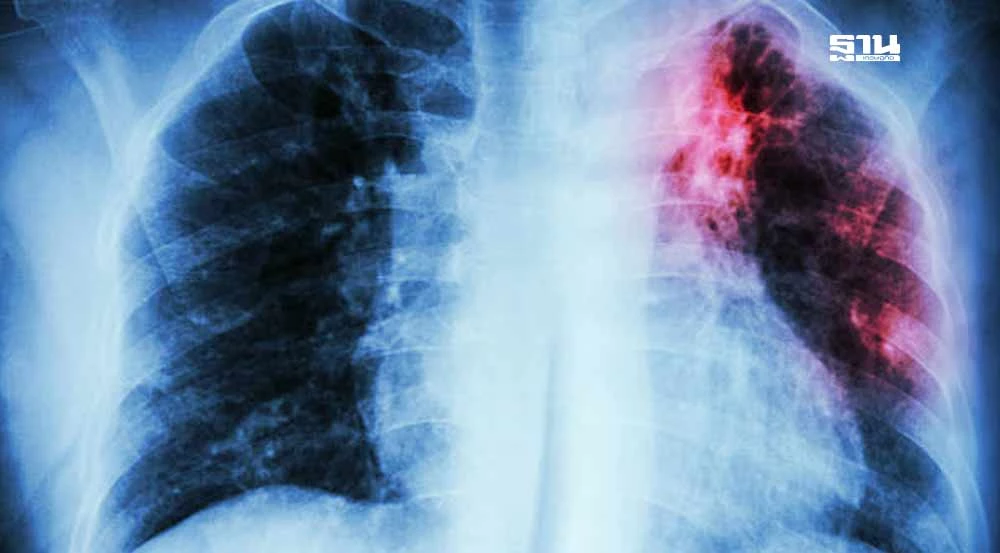

รู้หรือไม่ สูบบุหรี่ทำให้ปอดอ่อนแอ ลดภูมิคุ้มกัน เพิ่มความเสี่ยงในการติดเชื้อวัณโรคและทำให้โรคกำเริบหลังการรักษา

การสูบบุหรี่เพิ่มความเสี่ยงการติดเชื้อวัณโรค (TB) และยังเป็นสาเหตุสำคัญที่ทำให้วัณโรคที่อยู่ในระยะสงบกลับมาเป็นใหม่ได้ รวมถึงทำให้โรคมีความรุนแรงมากขึ้น

โดยมีผลต่อการฟื้นฟูและรักษาโรคได้ยากขึ้น ส่งผลให้ความเสี่ยงในการเสียชีวิตเพิ่มสูงขึ้นหลายเท่า การสูบบุหรี่ทำให้ภูมิคุ้มกันของร่างกายลดลง ส่งผลให้ปอดไม่สามารถกำจัดเชื้อวัณโรคที่หายใจเข้าสู่ปอดได้ดีเท่าคนที่ไม่สูบบุหรี่ การสูบบุหรี่จึงทำให้การรักษาวัณโรคไม่ประสบผลสำเร็จ และเพิ่มความเสี่ยงในการดื้อยา

การสูบบุหรี่ทำให้เกิดการอักเสบในปอดและทำลายเนื้อเยื่อปอดอย่างเรื้อรัง ส่งผลให้โครงสร้างของปอดเสียหายและระบบภูมิคุ้มกันลดประสิทธิภาพลง เมื่อปอดไม่สามารถกำจัดเชื้อวัณโรคได้อย่างมีประสิทธิภาพ เชื้อวัณโรคที่หายใจเข้าสู่ปอดก็จะเจริญเติบโตและแพร่กระจายได้ง่ายขึ้น

การสูบบุหรี่ยังส่งผลกระทบต่อการทำงานของระบบทางเดินหายใจ โดยทำให้การทำงานของปอดเสื่อมสภาพ และเพิ่มความเสี่ยงในการติดเชื้อจากภายนอก นอกจากวัณโรคแล้ว ยังเสี่ยงต่อโรคอื่น ๆ เช่น มะเร็งปอด, โรคปอดอุดกั้นเรื้อรัง (COPD), และปัญหาทางเดินหายใจต่าง ๆ การสูบบุหรี่ทำให้เยื่อบุทางเดินหายใจเสื่อมสภาพและไม่สามารถกำจัดสารพิษได้อย่างเต็มที่ ส่งผลให้ภูมิต้านทานลดลง รวมถึงความสามารถในการฟื้นตัวจากโรคต่าง ๆ เช่น วัณโรคก็ลดลงไปด้วย